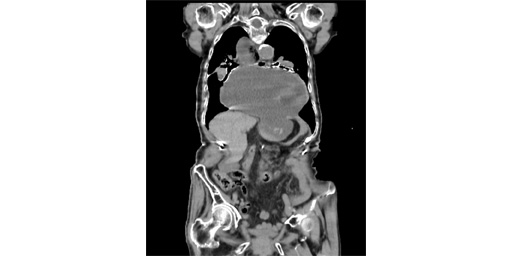

食道裂孔ヘルニアは、胃の一部が横隔膜の穴を通って胸腔内に侵入すると発生します。通常、食道裂孔ヘルニアは目立った症状を引き起こしません。ただし、より大きな食道裂孔ヘルニアの場合は手術が必要になる場合があります。

食道裂孔ヘルニアは、胃の一部が横隔膜の穴を通って胸腔に突き出るときに発生します。